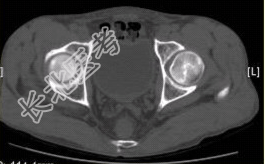

- [材料题] 男性,47岁。左髋部疼痛及压痛6个月,“4”字试验阳性。左髋关节内、外旋活动受限。检查提示:左髋关节活动轻度受限,大腿上部轻压痛。血常规检查正常。髋关节CT及MRI如下图。

- 多项选择题1.根据髋关节CT和MR影像,你认为此病例的影像学表现有

A、CT检查未见异常

B、左侧股骨头内可见线样高密度影

C、左股骨头塌陷变扁,其内可见条带状硬化

D、左股骨头内见蜿蜒走行的T

信号F、左髋关节间隙变窄

- 多项选择题2.对本病例,你首先考虑的诊断是

B、左股骨头缺血性坏死

- 多项选择题3.股骨头缺血性坏死早期诊断的最佳影像学检查方法是

A、CT

B、MRI